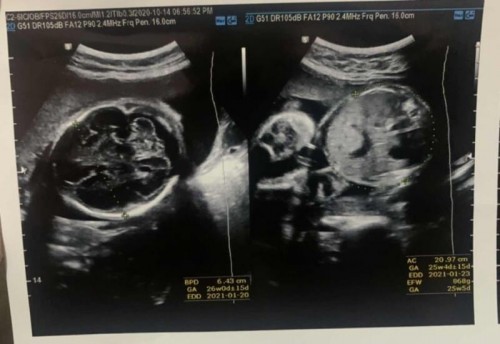

Udah USG kehamilan? Dikasih kertas hasil USG dan dijelasin, tapi kadang lupa. Liat di kertas USG nya, tapi bingung dengan singkatan-singkatan di hasil USG. Berikut beberapa singkatan yang terdapat pada hasil USG mom : • LMP (Last Menstrual Period) : Hari pertama haid terakhir • EDD (Estimated Delivery Day) : Perkiraan persalinan berdasarkan tanggal menstruasi • GA (Gestational Age) : Perkiraan umur kehamilan, pengukurannya berdasarkan pada panjang tungkai lengan ataupun diameter kepala • BPD (Biparietal Diameter) : Ukuran tulang pelipis kiri dan kanan. Digunakan untuk mengukur janin di trimester dua atau tiga • HC (Head Circumferencial) : Lingkaran kepala, digunakan untuk mengukur usia kehamilan di trimester dua atau tiga • AC (Abdominal Circumferencial) : Ukuran lingkaran perut bayi. Biasanya pengukuran disatukan dengan pengukuran BPD dan akan menghasilkan perkiraan berat bayi, digunakan untuk mengukur kehamilan di trimester dua atau tiga • FL (Femur Length) : Ukuran panjang tulang paha bayi digunakan untuk mengukur kehamilan di trimester dua atau tiga • FW (Fetal Weight) : Berat janin • EFW (Estimation Fetal Weight) : Perkiraan berat bayi • FTA (Fetal Trunk Abdominal) : Merupakan panjang badan • GS (Gestasional Sac) : Merupakan ukuran kantong kehamilan berupa bulatan hitam, digunakan untuk mengukur kehamilan di trimester pertama • CRL (Crown Rump Length) : Ukuran jarak dari puncak kepala ke ekor bayi, digunakan untuk mengukur usi kehamilan di trimester pertama • F-HR (Fetal Heart Rate) : Frekuensi jantung bayi #pregnancy #Usg